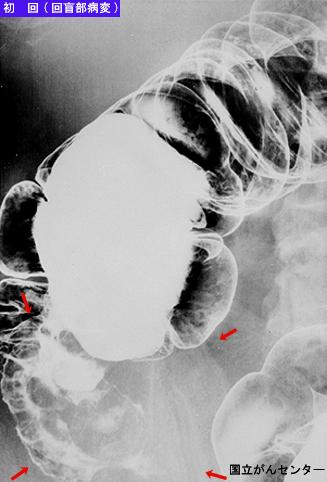

Criteria of Hist.ClassificationMalignant Lymphoma/Malignant lymphoma

LocationLarge intestine(Colon)/Ilenocecal region

Technique, MethodX-ray

Macroscopic TypesType 1 Protuberant (polypoed) type/

Size40 -